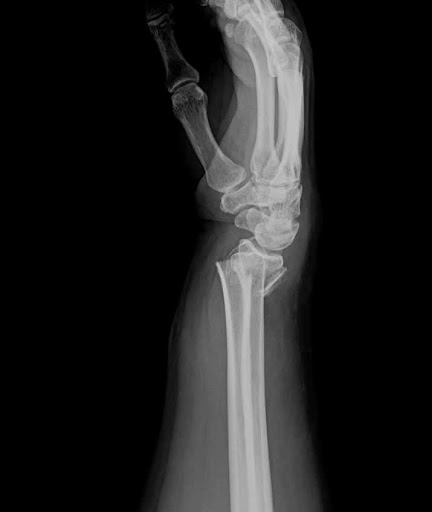

- Tổn thương chủ yếu là mất chất khoáng ở xương xốp (xương bè). Biểu hiện là sự lún xẹp các đốt sống, gãy xương tại đốt sống hoặc gãy xương Pouteau – Colles.

Gãy Pouteau – Colles